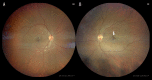

BACKGROUND COVID-19 is the disease caused by the novel virus, severe acute respiratory syndrome Coronavirus 2 (SARS-CoV-2). The spectrum of disease seen in patients with COVID-19 infection ranges from asymptomatic or mild symptoms to severe pneumonia and even acute respiratory distress syndrome, which often requires invasive ventilation and intensive care. COVID-19-associated infection can be catastrophic, leading to both arterial and venous occlusion, microinfarcts, and multiorgan failure, although retinal vein occlusion has not yet been reported. CASE REPORT We present the case of a 40-year-old man who presented with a 3-day history of shortness of breath, cough, and fever. He also reported right calf pain and blurring of vision in both eyes. His medical history included hypertension and morbid obesity. The patient was found to have severe COVID-19 pneumonia on high-resolution computed tomography of the chest, right leg deep venous thrombosis on Doppler ultrasonography, and bilateral central retinal vein occlusion (RVO) on fundal examination. He was started on full-dose anticoagulation and discharged on rivaroxaban for 3 months. After 2 weeks of therapy, he had fully recovered from his COVID-19 symptoms and had near-normal vision. CONCLUSIONS COVID-19 infection can cause RVO. Early full-dose anticoagulation should be considered in high-risk patients with severe COVID-19 infection. Ophthalmologists and other clinicians should have a high index of suspicion for RVO in patients with COVID-19 infection who presenting with blurred vision and severe pneumonia.

Figures